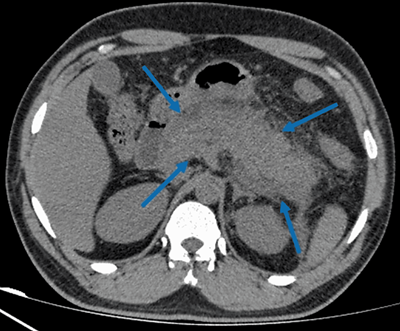

腹部超声检查未发现任何胆管扩张、胆石症或胆囊炎征象。腹部CT

检查显示胰腺肿胀,边界不清,与急性胰腺炎

诊断一致(图1)。随后患者接受静脉补液、镇痛、止吐等支持性治疗措施。

(图1 腹部CT检查)